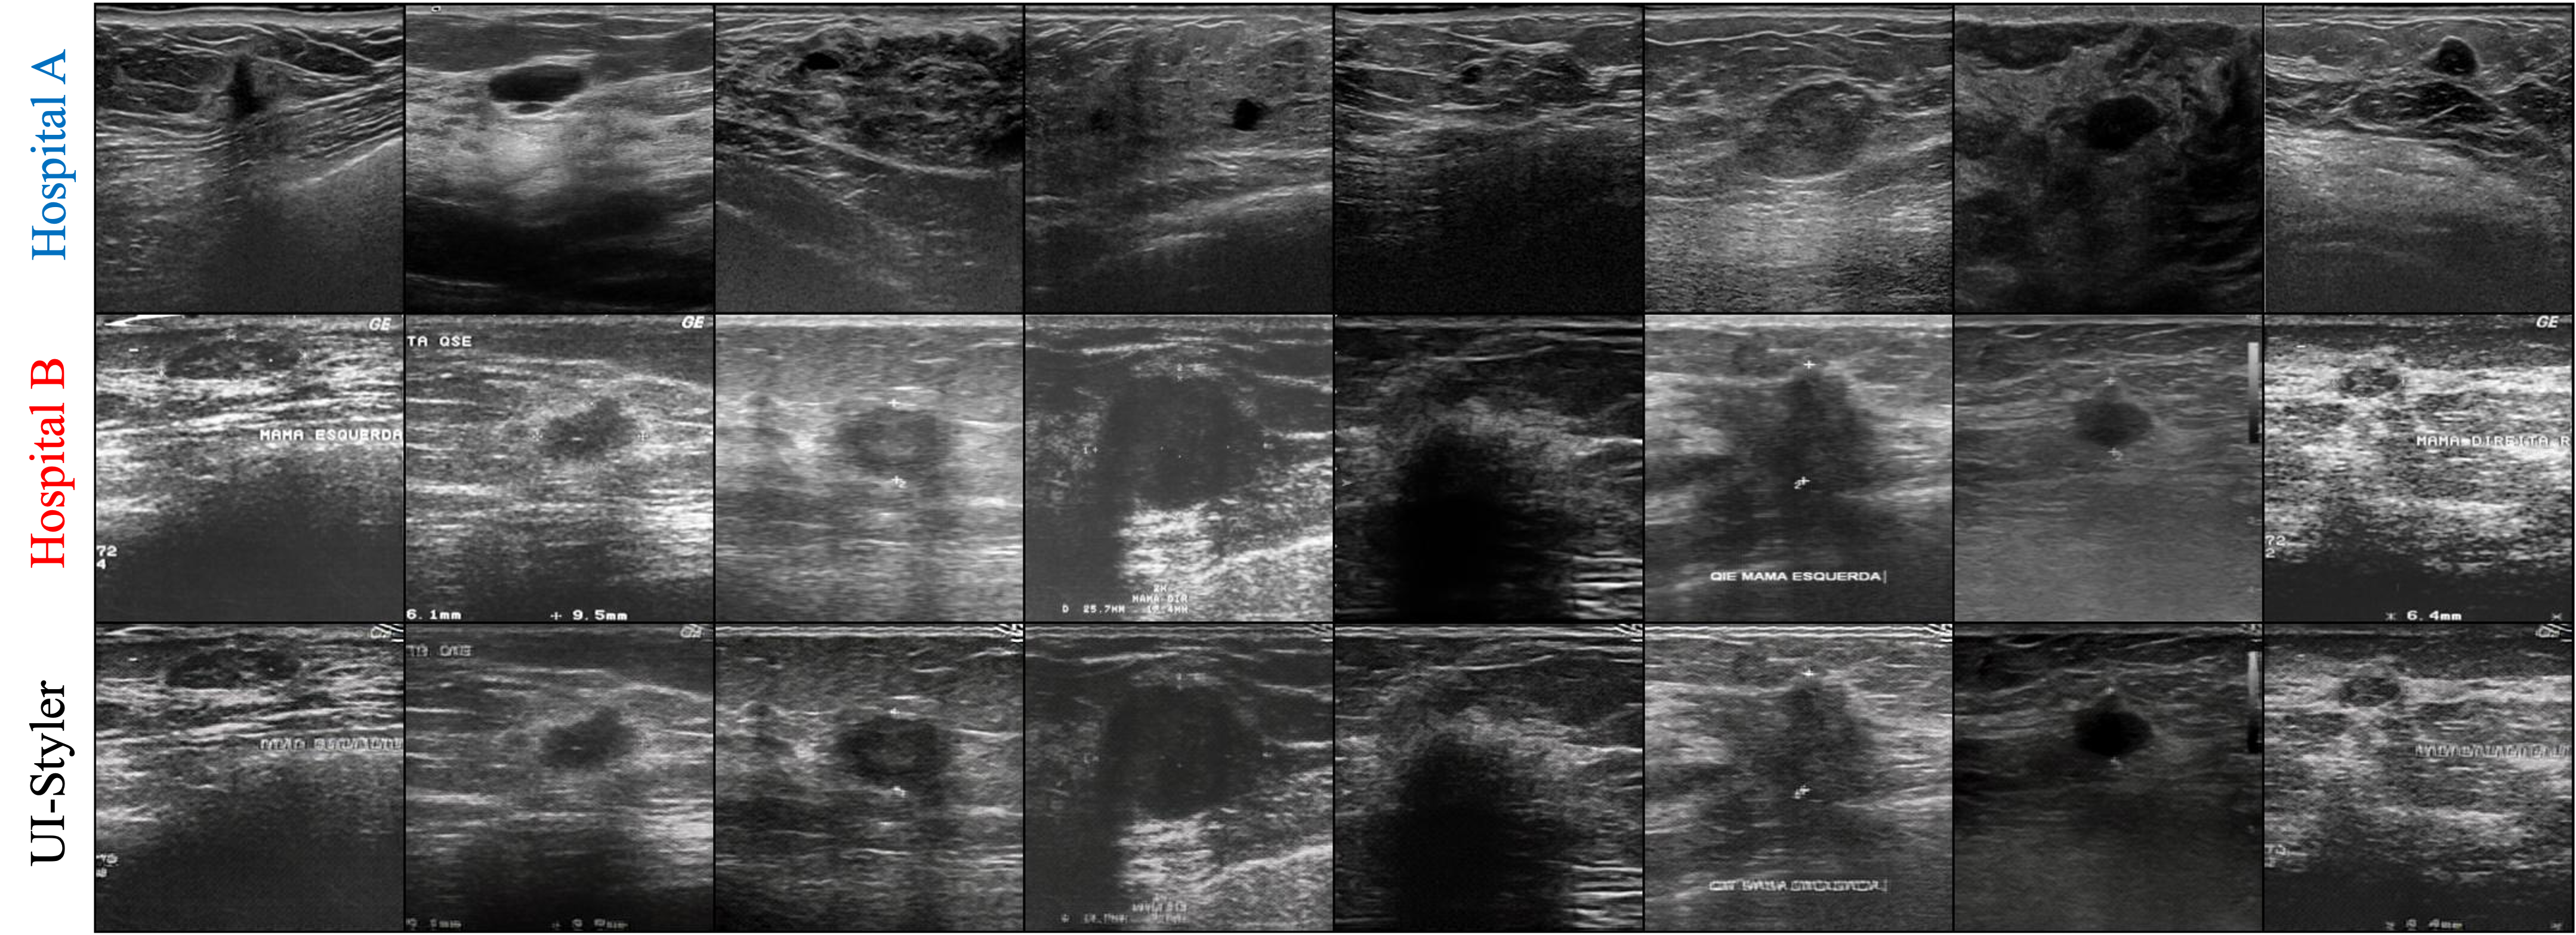

🖼️ Visual Results